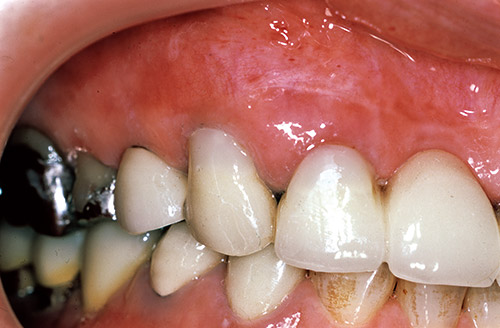

図12~18に前歯部メタルボンド修復歯の歯頸部根面露出に伴う複数歯の補修修復の症例を示す。

本症例では、トライエスボンドNDとポーセレンボンドアクチベーターの混和物がボンディング材として用いられた。

図17 仕上げ後。

図18 研磨後。